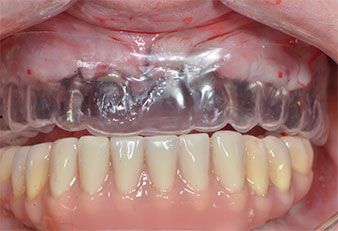

A flame-shaped, diamond-coated piezoelectric instrument (Piezomed I1) was used to mark the implant positions and to perform pilot preparation (Fig. 3). Care was taken to use an up and down movement, with reduced power, full irrigation and low pressure (below 300 g). Next a pilot instrument (Piezomed I2A/I2P) was applied for the initial 2 mm diameter enlargement of the implant sites (Fig. 4), followed by a 3 mm insert (Fig. 5).

Due to the relatively hard bone (D2) in this area, the 10 mm long implant sites at positions 11 and 21 were finalized with a 4 mm diameter rotary drill, in combination with a W&H WS-75 L surgical contra-angle handpiece, the W&H Implantmed implant motor and the optional W&H Osstell ISQ module. In contrast, due to the soft bone the posterior sites were prepared to a final 3 mm diameter using the Piezomed I3P instrument. The implants were finally placed transgingivally to osseointegrate for three months (Figs. 6-10). The existing denture was retained on four provisional implants (Fig. 8).